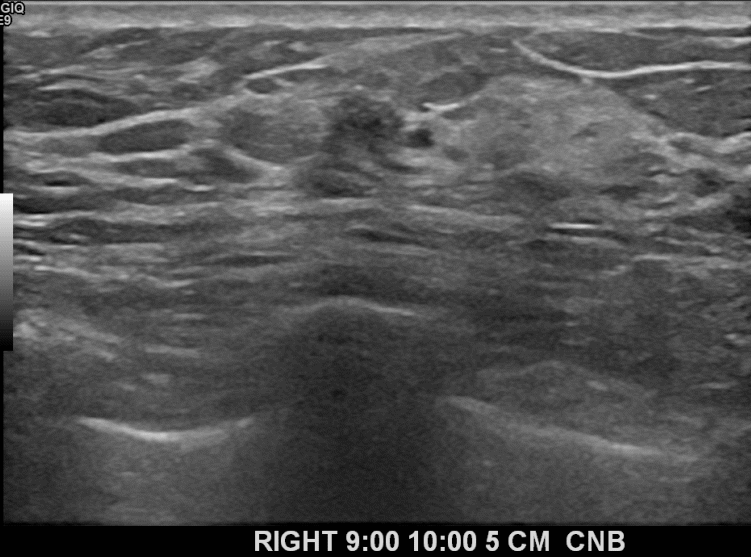

상기환자 경과관찰중이신 40대후반 여성분으로 의심스러운

우측혹 조직검사 시행해 상피내암으로 진단되었습니다